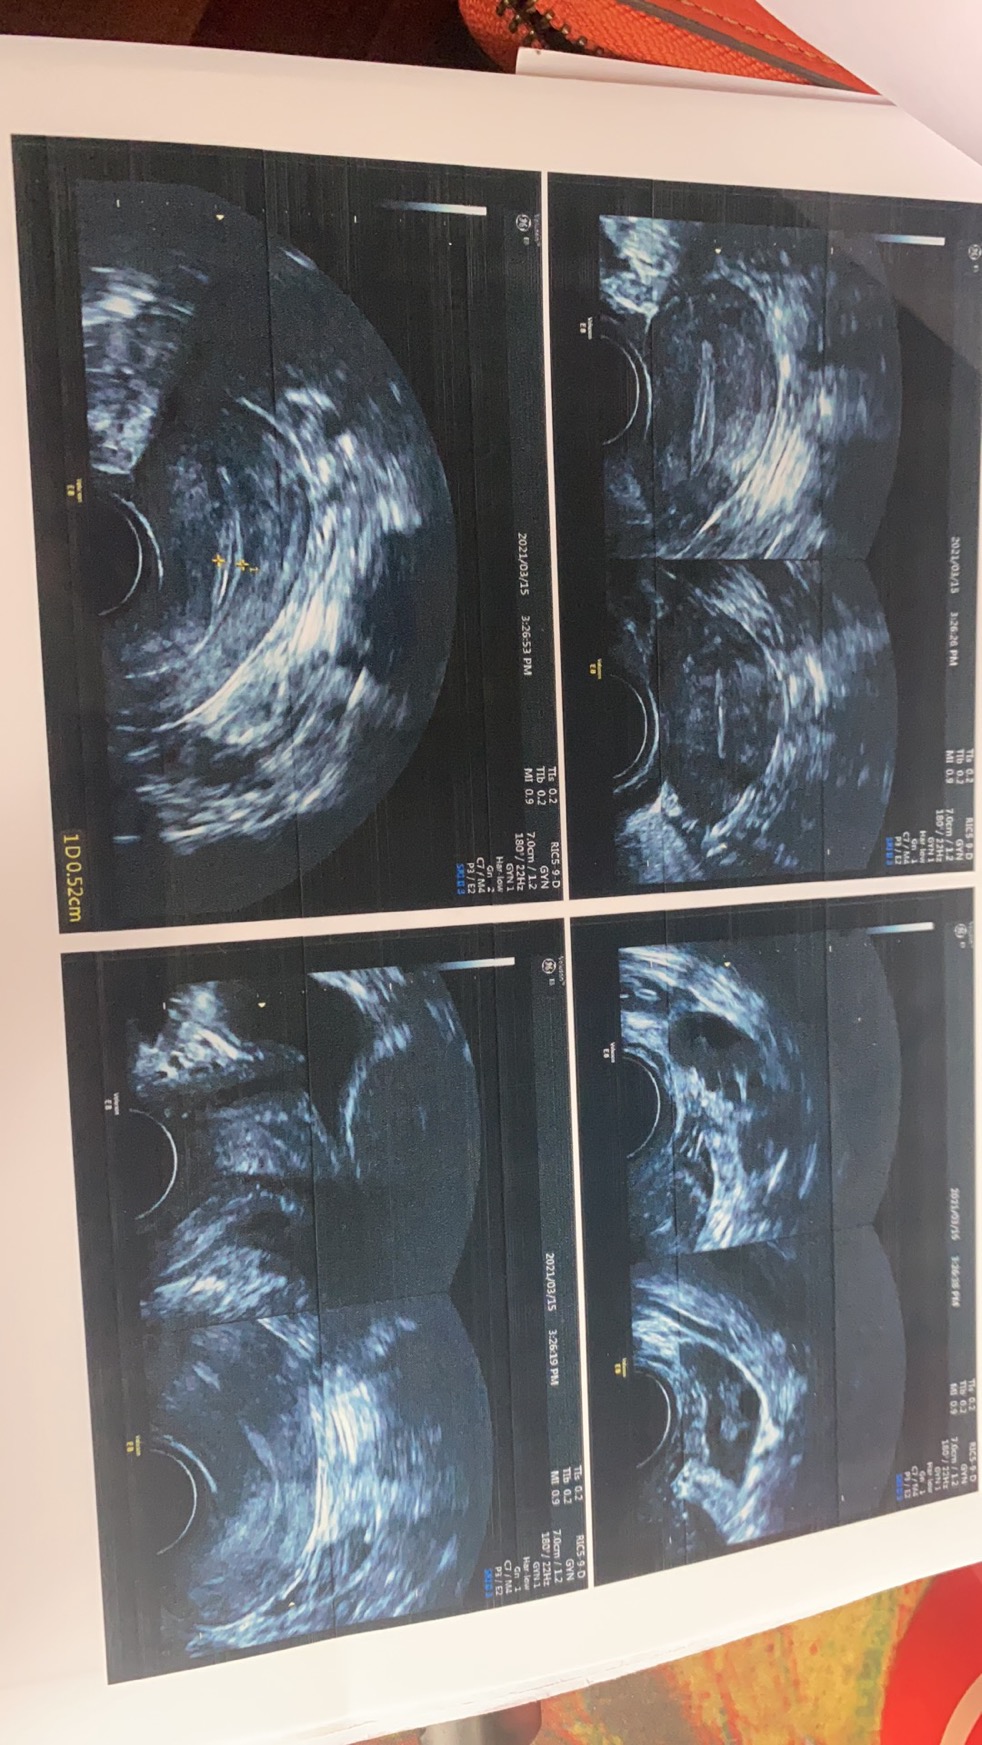

医生,您好,麻烦您帮我看一下我做的三维彩超报告,是否有粘连,我这个是否是桶状的宫腔呀?我这个彩超是排卵前10天照的,因为一年前右侧宫角膜性粘连,分粘过的,这个月例假还没来,非常害怕,是不是复粘成重度,所以闭经了。

您好,宫腔很好,没有粘连。现在是月经第几天了,没有优势卵泡,内膜也很薄。

匿名用户 回复 王小婷:谢谢医生,这是我排卵前10天照的,我有多囊倾向,雌激素低,卵泡长得特别慢,内膜也长得很慢,我排卵当天,内膜才7毫米,我这个确定没有粘连吗?我就是很怕

王小婷 回复 匿名用户:是的,没有粘连。卵泡长的慢,建议查下基础内分泌,甲功,胰岛素抵抗和糖耐量看下有没问题。

根据检查结果来看宫腔没有粘连,月经不来与子宫内膜太薄有关系,可以多吃豆制品促进子宫内膜增长及卵泡发育,最好月经第二到四天化验激素六项水平看看。避免生冷辛辣刺激性食物及经常熬夜。